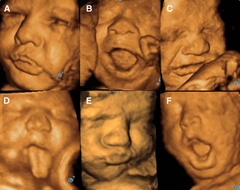

Ultrassom 5d Imagens Mais Nitidas E Detalhadas Do Bebe Revista